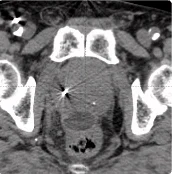

215 cc prostate post-CT showing BioProtect Balloon Spacer, prostate, and rectum.

Post-CT

Image courtesy of Dr. Shawn Zimberg, Radiation Oncologist.